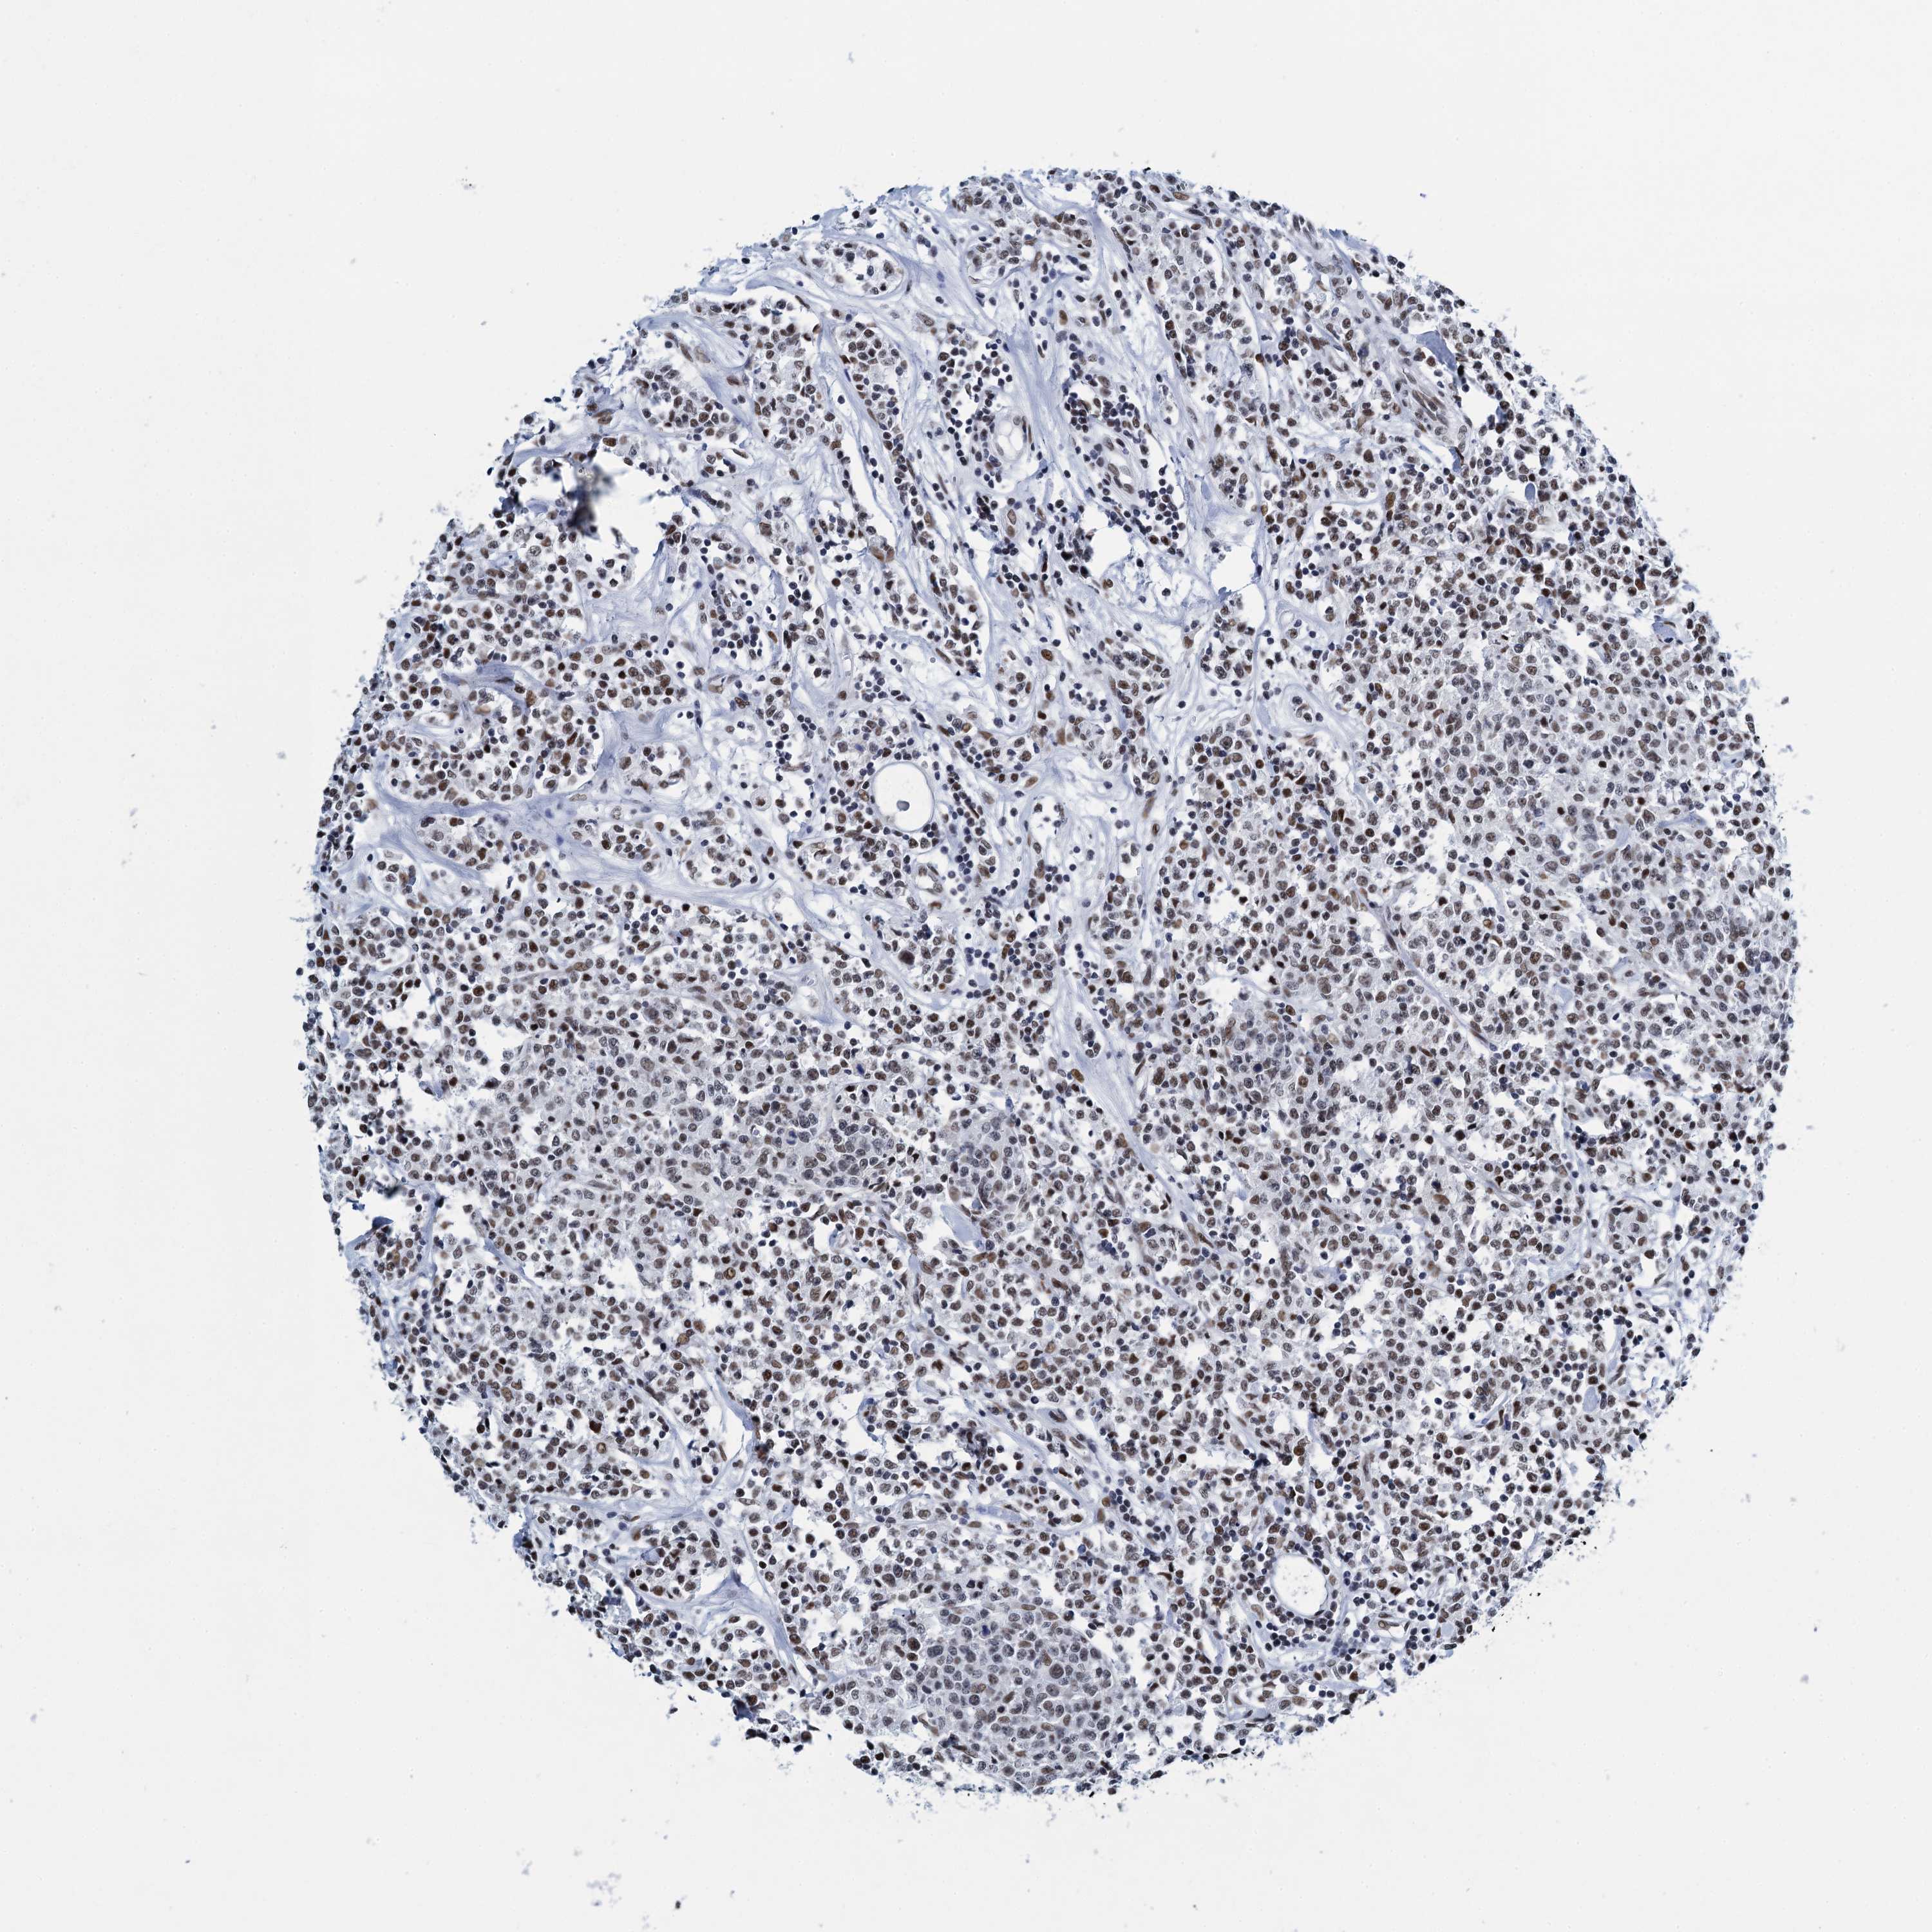

CANCER LYMPHOMA Show tissue menu

LYMPHOMA - Protein expressioni

A mouse-over function shows sample information and annotation data. Click on an image to view it in a full screen mode. Samples can be filtered based on level of antibody staining by selecting one or several of the following categories: high, medium, low and not detected. The assay and annotation is described here.

Antibody stainingi

Antibody staining in the annotated cell types in the current human tissue is reported as not detected, low, medium, or high, based on conventional immunohistochemistry profiling in selected tissues. This score is based on the combination of the staining intensity and fraction of stained cells.

Each image is clickable and will lead to virtual microscopy that enables deeper exploration of all samples and also displays staining intensity scores, fraction scores and subcellular localization as well as patient and tissue information for each sample.

Antibody HPA041632

Hodgkin's disease, NOS

Malignant lymphoma, non-Hodgkin's type, High grade

Malignant lymphoma, non-Hodgkin's type, Low grade